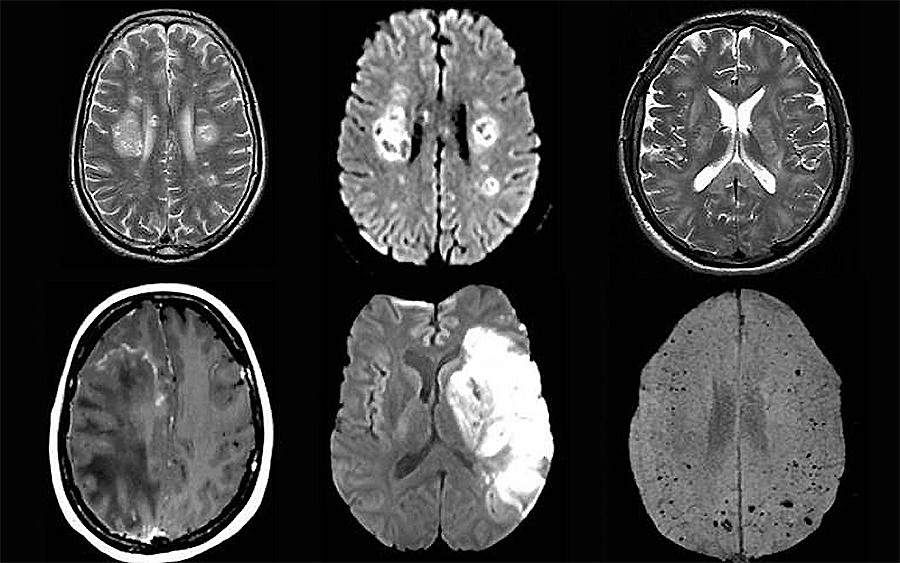

Коронавирус может поражать нервную систему и головной мозг, влиять на психоэмоциональное состояние. Данные свидетельствуют о том, что после заражения COVID-19 у некоторых людей наблюдается стойкая хроническая усталость и другие психоневрологические проблемы [3].

Нервно-психические расстройства могут возникать либо в результате прямого воздействия инфекции на ЦНС, либо косвенно: через иммунный ответ организма или медикаментозную терапию.

В частности, неврологические осложнения COVID-19 могут включать делирий (спутанность сознания), воспаление мозговых тканей, инсульт и повреждение нервов, — установлено в исследовании 2020 года [4].

Причем у зараженных коронавирусом может не быть серьезных респираторных симптомов (простуда, кашель и т.п.), а неврологическое расстройство является первым и основным проявлением COVID-19.

Также исследователи выявили редкое и иногда смертельное заболевание, известное как ADEM (Acute disseminated encephalomyelitis — острый диссеминированный энцефаломиелит, характеризующийся внезапным развитием воспаления в головном и спинном мозге), распространенность которого, по всей видимости, растет из-за пандемии.